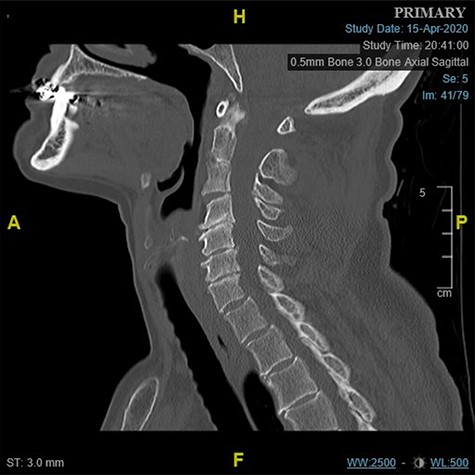

The left shoulder radiograph showed no abnormality. The sagittal images of the cervical spine CT scan are shown in Figs 1 and 2a and b. Figure 1 is the mid-sagittal slice of the CT scan at presentation and shows no obvious malalignment.

Midline sagittal CT scan of the cervical at the time of first presentation.